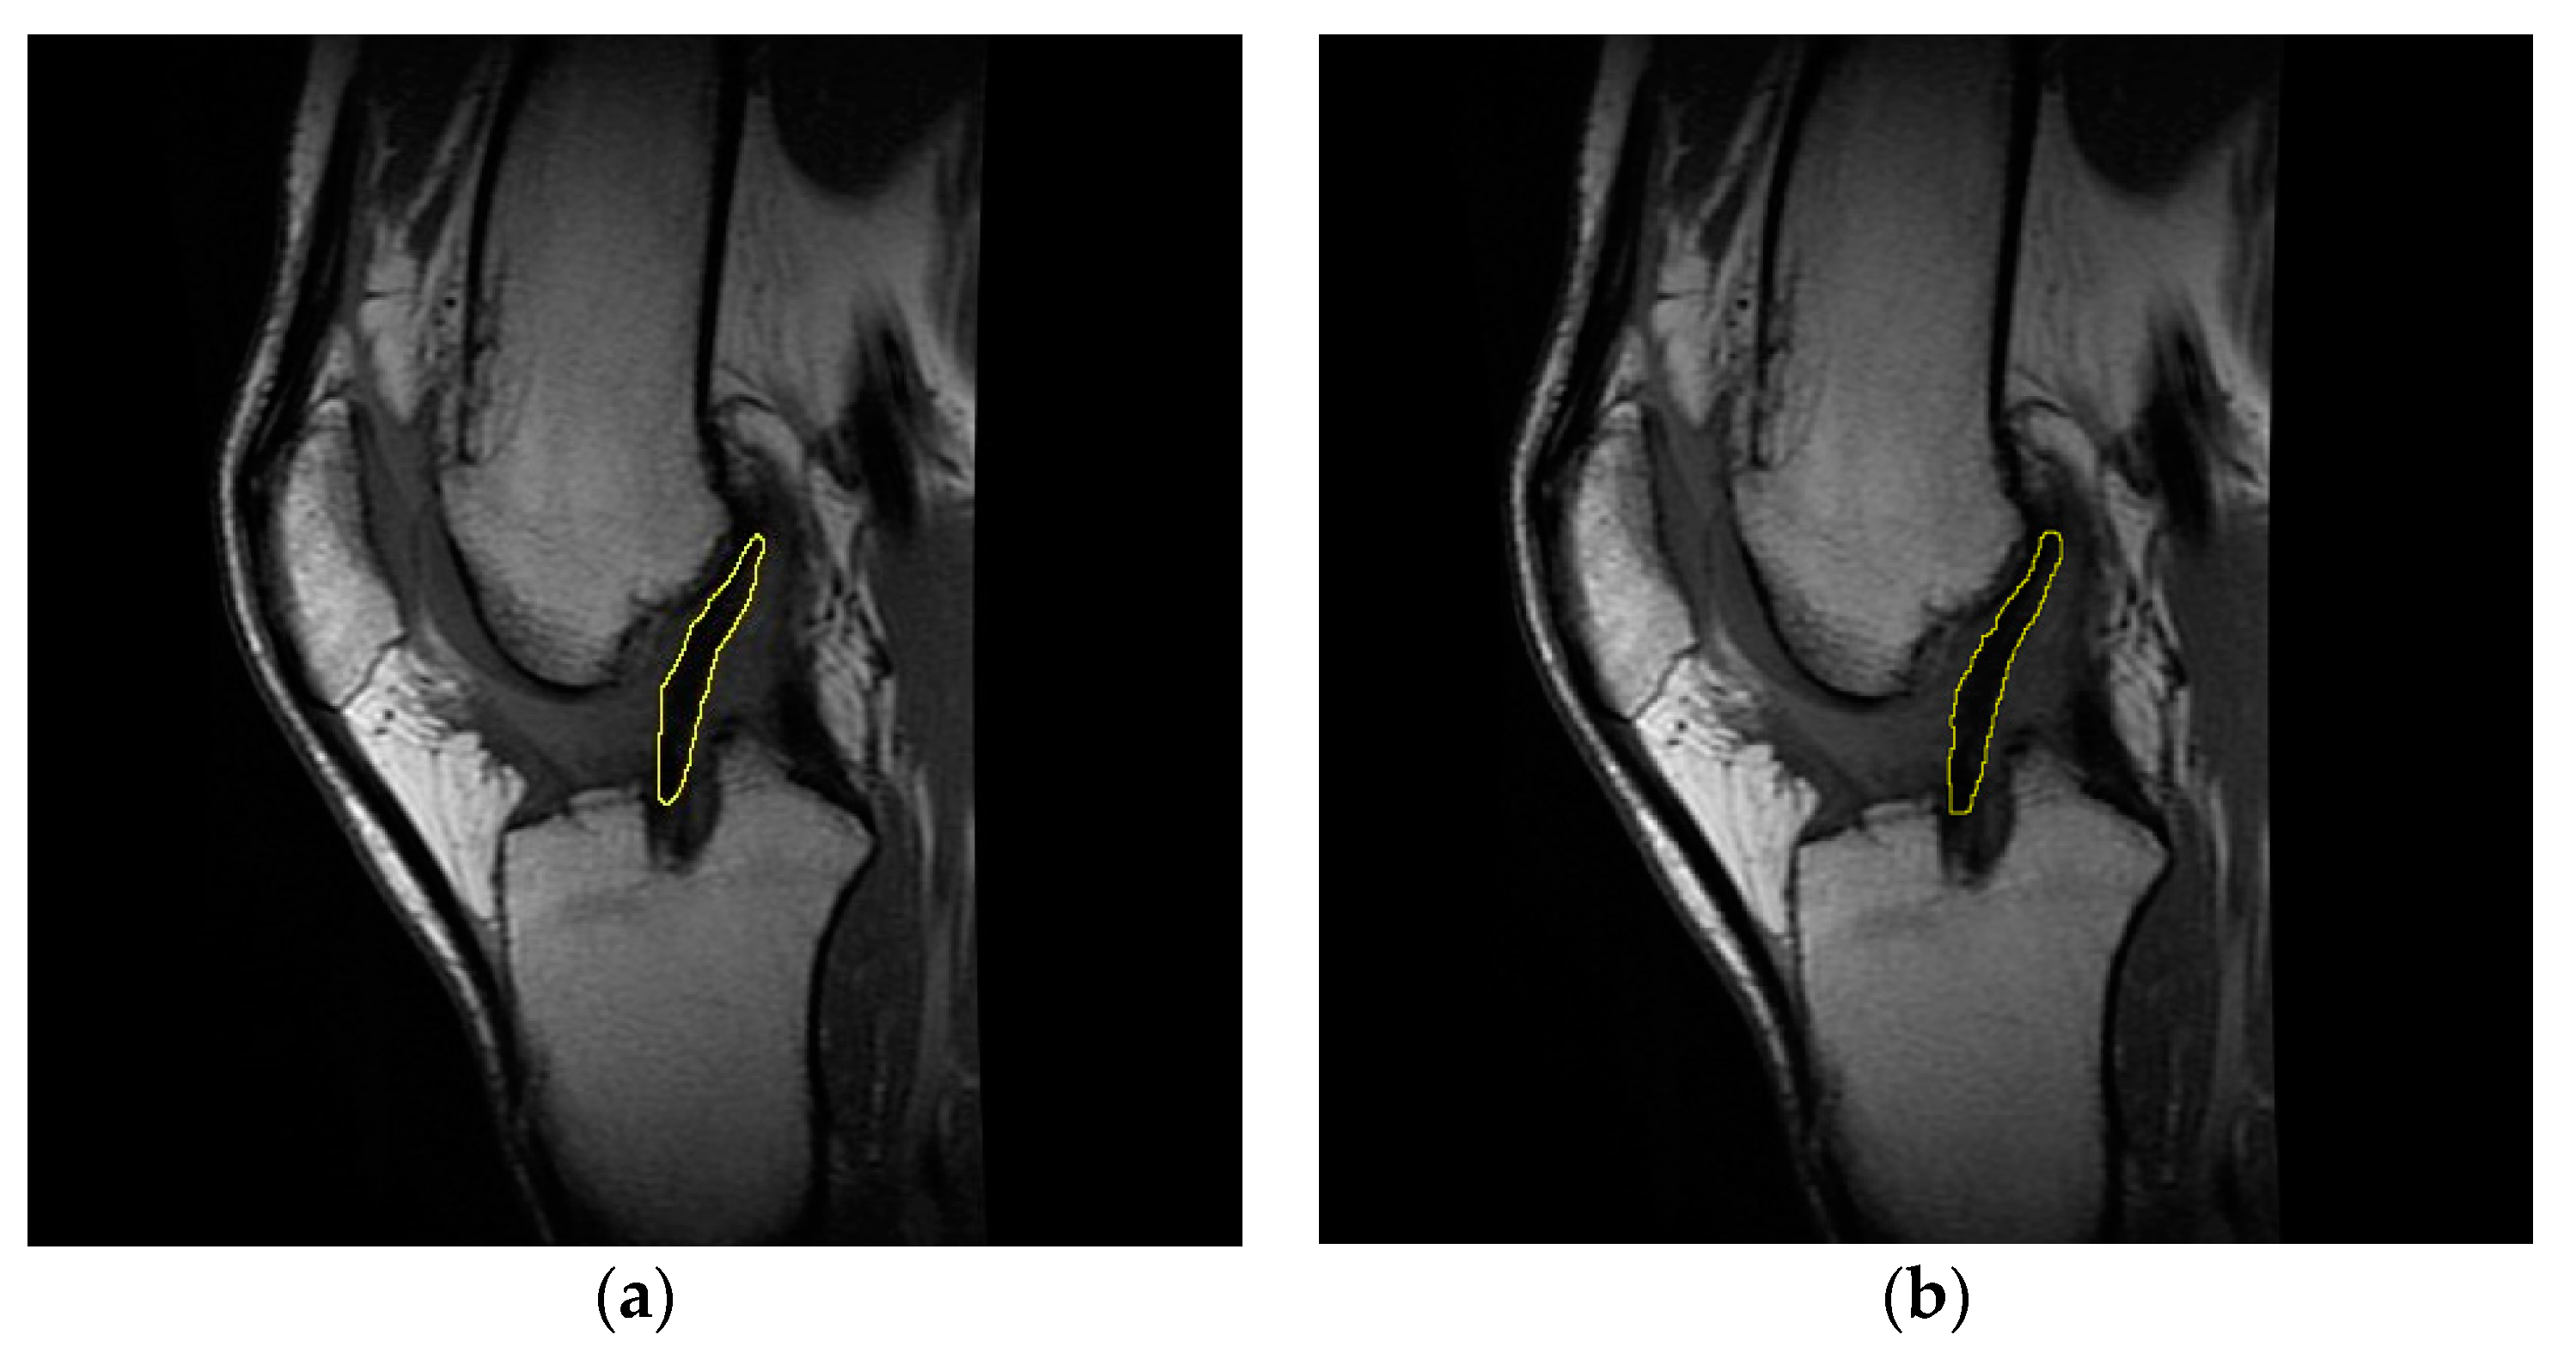

Concerning the evaluation of the T2 signal for the injured ligament, healthy ligament, and graft, the slice of each sagittal sequence showing the clearest image of Blumensaat’s line was selected [31,32]. From this perspective, the use of a single section to acquire the T2 signal allows for the exclusion of undesirable factors such as magnetization transfer and crosstalk; these issues might indeed occur if a multi-section acquisition is used [33,34]. After obtaining the T2 map by applying the Levenberg–Marquardt algorithm [35], the contours of the intra-articular portion of the graft/ACL were manually outlined on the mask obtained by overlaying the starting slice to the corresponding region in each T2 map image [36] (Figure 1). This procedure allowed us to evaluate the T2 signal of the purely tendinous/ligamentous portion, achieving substantial segregation from surrounding synovial tissue, which usually occurs throughout the course of graft maturation [37].

Representative sagittal images of the graft intra-articular portion, manually outlined on the starting slice (a) and on the mask obtained by overlaying the latter to the T2 map (b). Data concern subject #6 at four months follow-up.